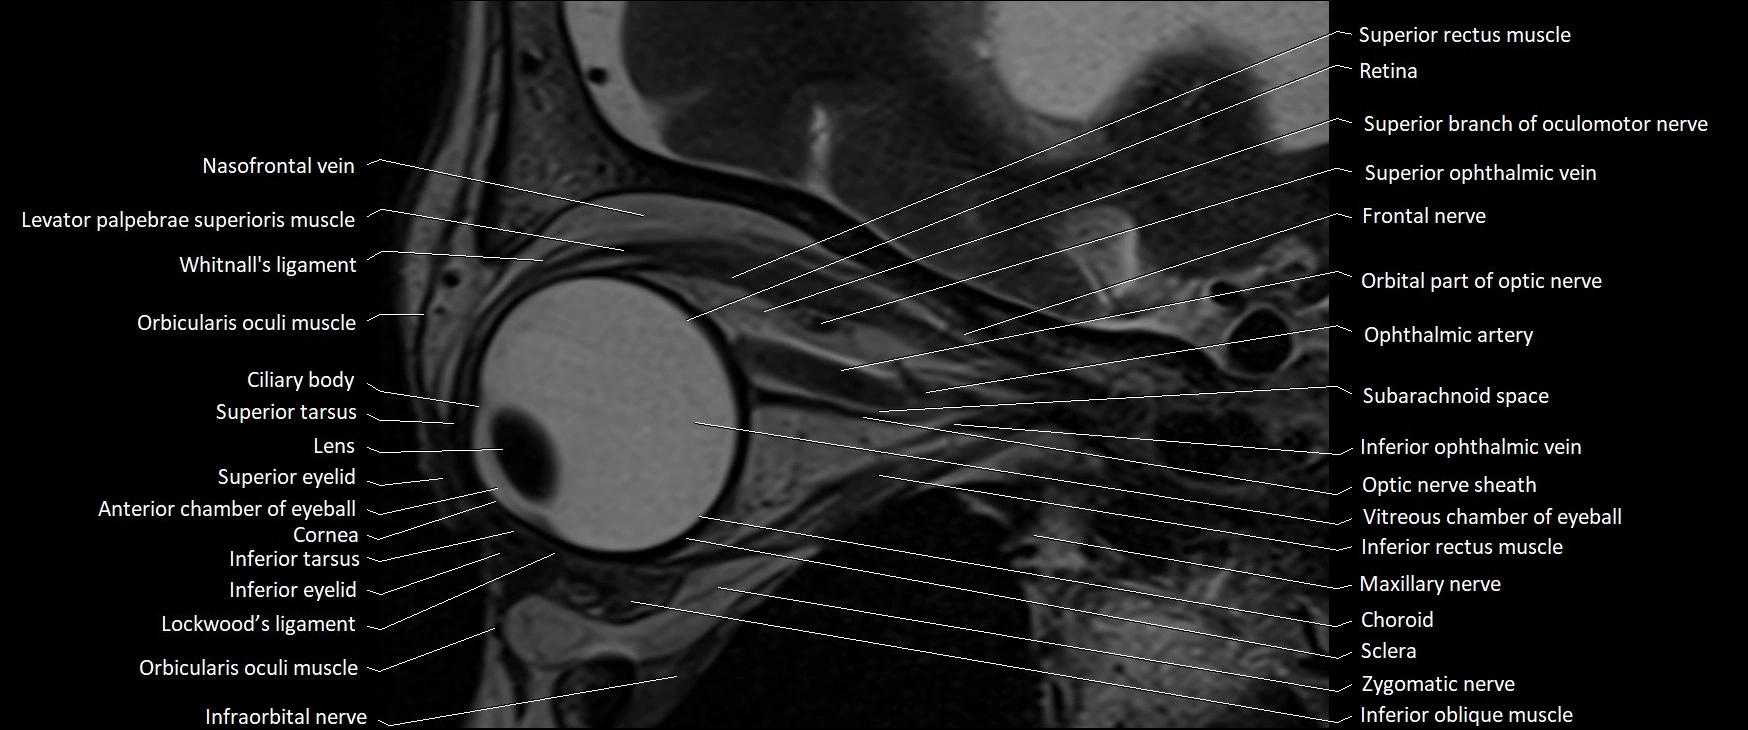

- Anterior chamber of eyeball

- Cornea

- Inferior eyelid

- Inferior oblique muscle

- Inferior ophthalmic vein

- Inferior rectus muscle

- Infraorbital nerve

- Intracanalicular part of optic nerve

- Lacrimal gland

- Levator palpebrae superioris muscle

- Lockwood’s ligament

- Nasofrontal vein

- Oculomotor nerve (Superior branch)

- Orbicularis oculi muscle

- Retina

- Retrobulbar fat

- Sclera

- Superior eyelid

- Superior ophthalmic vein

- Superior rectus muscle

- Superior tarsus

- Vitreous chamber of eyeball

- Whitnall's ligament